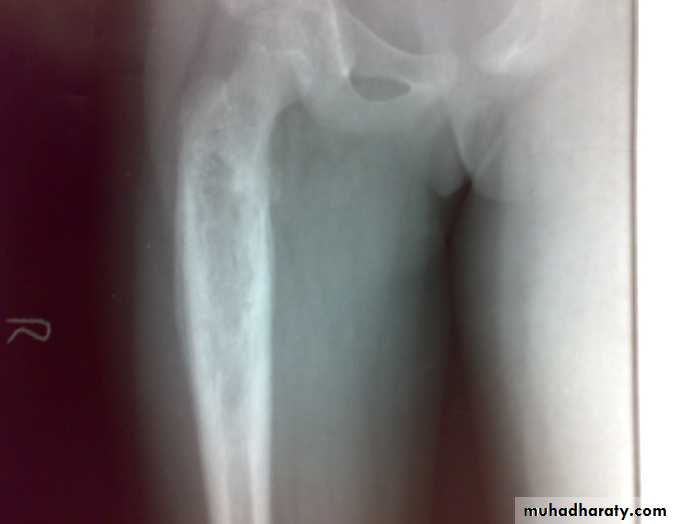

: X-ray are very variable but it show combination of bone destruction and bone formation.

The metaphysis show osteolytic and osteoblastic areas, the cortex is usually perforated and soft tissue shadow may be seen.

There is new bone formation in form of Codman's triangle at periphery of when cortex penetration cause periostium elevation and vertical streaks of calcification in the adjacent soft tissues called sunray appearance.